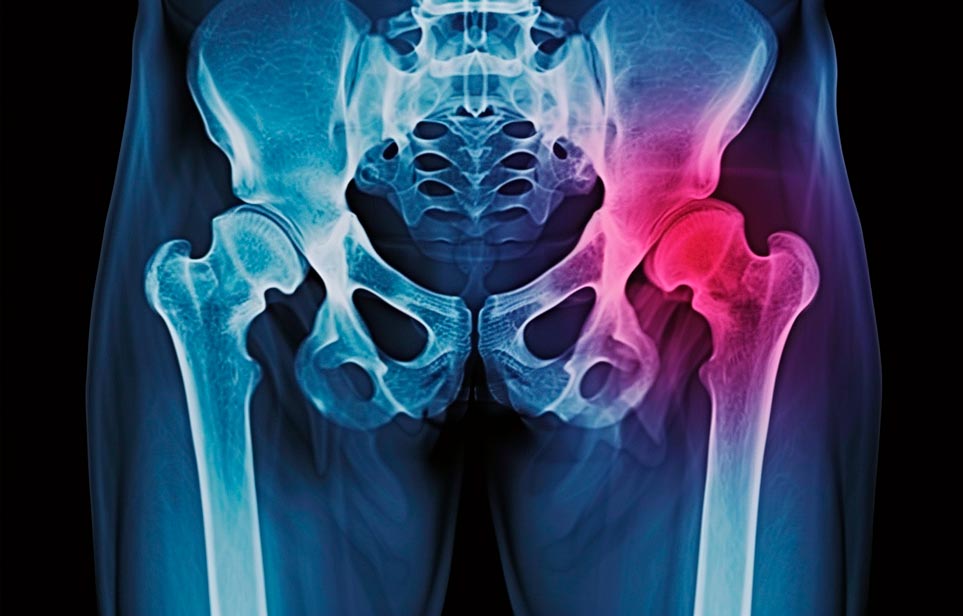

Реабилитация пожилых после перелома шейки бедра в Щелкино

Такая травма в большей части случаев возникает у граждан преклонного возраста. При её появлении на протяжении длительного времени сохраняются болевые и неприятные ощущения в области паха, при которых серьёзно ухудшается качество жизни, возникает множество последствий для его жизни и здоровья.

По какой симптоматике можно определить перелом шейки бедра?

Выявить его можно по возникновению следующей тревожной симптоматики:

- Визуально повреждённая нога сокращается на несколько сантиметром из-за сокращения мышц.

- Стопа выворачивается наружу.

- В лежачем положении человек не может поднять ногу.

При такой симптоматике важно незамедлительно обращаться к специалистам для получения всей необходимой помощи, терапии и восстановления после перелома шейки бедра. Если не оказать помощи старику, то это приведёт к гноению, инвалидности, иным видам осложнений.